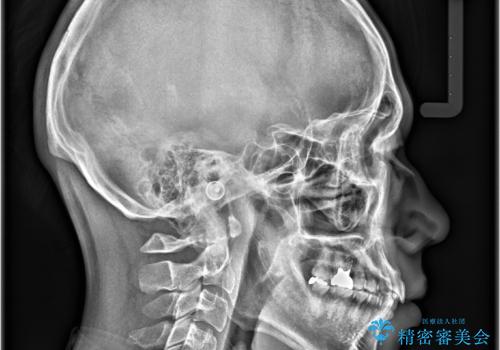

- 主訴:上下前歯の凸凹を治したい、下の前歯が見えないのも改善したい

叢生の改善、前歯被蓋量の改善、顔に対しての正中の改善をインビザラインにて行いました。

モデレートパッケージは作製可能枚数26枚という枚数制限があるため、臼歯部はあまり大きな動きはしない設計にしています。

正中を合わせるため、マウスピースの装着とともに顎間ゴムも使用していただきました。

治療期間:12か月

リファイメント回数:2回